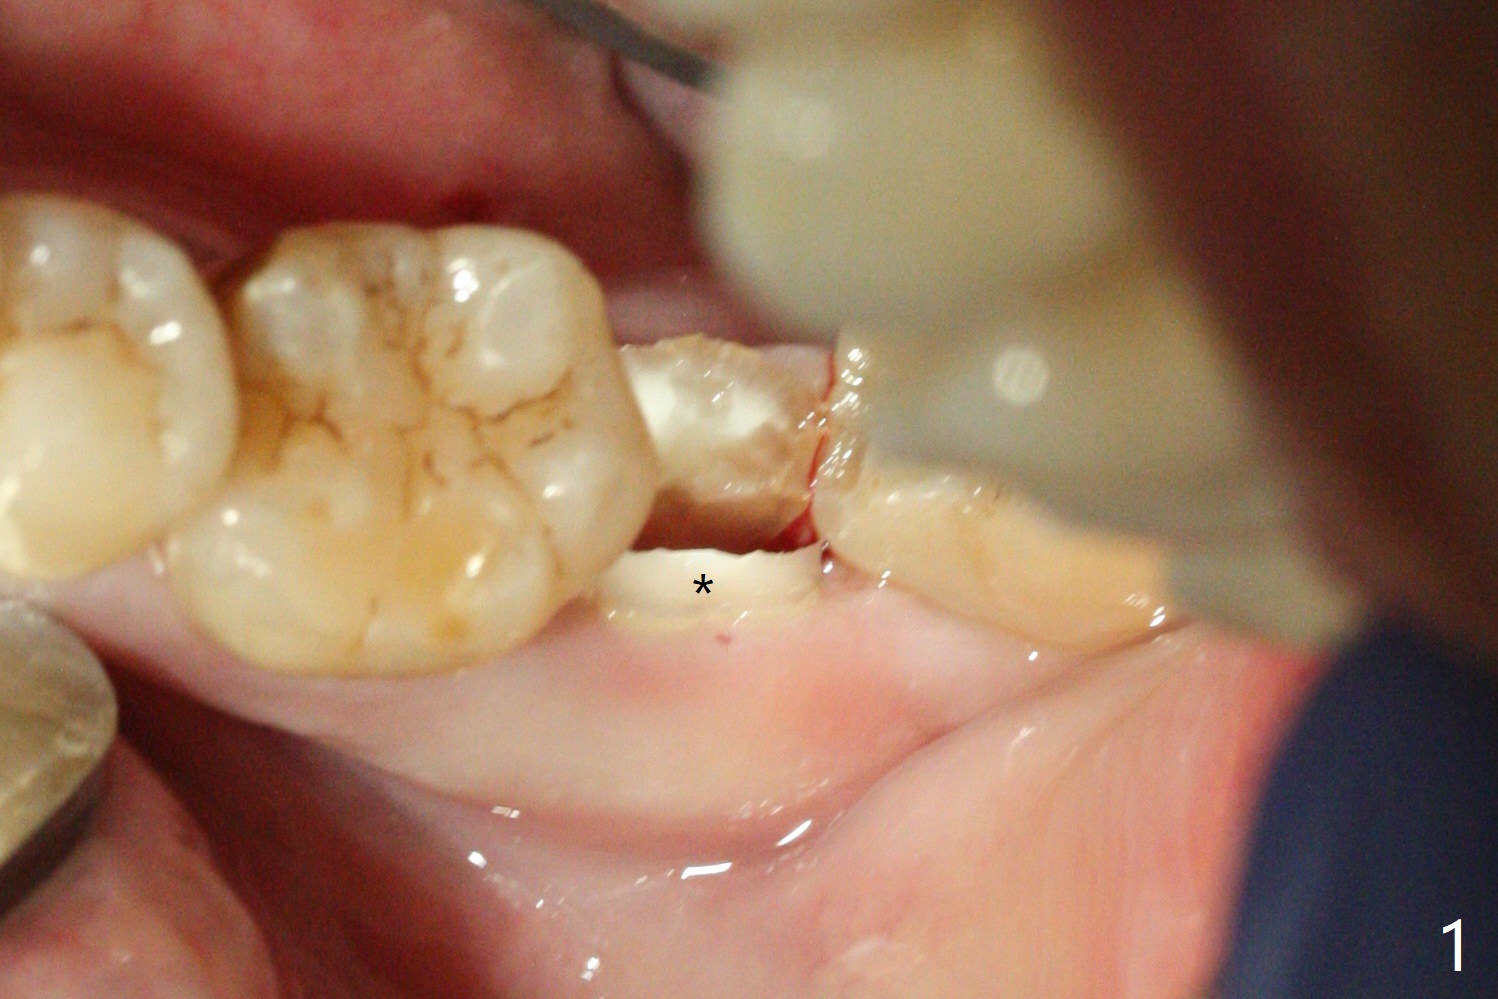

Socket shield (partial extraction therapies) is going to be conducted in this case to form a substitute buccal plate of the 2nd molar (Fig.1 *). The apex of the shield that contacts the 4.5x10 mm dummy implant cannot be removed because of poor access (Fig.2 * (12 mm offset)). Due to high bone density, a 4.5 mm drill has to be used in order to place a 5x7.3 mm definitive implant (Fig.3). In spite of the fact that the implant seems to be completely seated, the implant is ~ 1 mm supracrestal lingually. After implant removal, a 4.5x11.5 mm drill cannot reach the depth due to high bone density. 800 RPM instead of 50 RPM may help. When the implant is reseated, it appears to be .5 mm deeper than before clinically, although it looks incompletely seated in X-ray (Fig.4 <). The insertion torque is 60 Ncm. Allograft mixed with PRF is placed around the implant with cover screw, particularly mesiolinguodistal (Fig.4 *). The sockets of #17 and 18 are approximated with the help of 2 piece of PRF and collagen plug. The wound dehisces 9 days postop (Fig.5,6), although asymptomatic. Forced closure of the sockets with suture seems unnatural. An immediate provisional should have been fabricated. CT shows possible loss of part of bone graft (Fig.7). Regraft seems necessary in the appointment of uncover. Antibiotic is prescribed for another week. The gingiva seems healthy around the exposed healing screw 16 days postop (Fig.8). After debridement, the healing screw is then changed to a 4.5x5 mm healing abutment. The majority of the bone graft is lost without immediate provisional in 4 months (Fig.9 * (<: socket shield)). Then a 5.5x5 mm healing abutment is inserted for impression next appointment. A 5.2x4.5(4) mm cemented abutment is placed before impression (Fig.10). With socket shield (Fig.11 ^), the buccal gingiva looks more keratinized than the lingual one (Fig.12 *). Photos are taken immediately pre-cementation. Socket shield (*) covers the implant and abutment buccally (Fig.13 CT taken immediately pre-cementation).